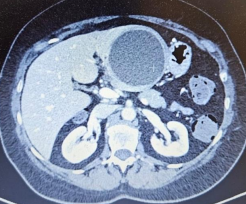

Per la prima volta in tutta l’Italia centro-meridionale, è stato eseguito presso la Casa di Cura “Regina Pacis” di San Cataldo (CL) un intervento di Lobectomia Epatica sinistra con l’utilizzo del sistema Robotico Versius™. Fino ad oggi, questo tipo di intervento veniva eseguito solo con tecnica tradizionale (chirurgia aperta) oppure in laparoscopia. Il delicato intervento chirurgico si è reso necessario a causa della presenza di una voluminosa neoformazione cistica che interessava la quasi totalità dell’intero lobo epatico sinistro e che era responsabile di importanti disturbi digestivi da compressione sullo stomaco. L’intervento chirurgico, dall’altissimo coefficiente di difficoltà, è stato condotto con successo dal Responsabile del Modulo di Chirurgia Epatobiliopancreatica della Casa di Cura “Regina Pacis”, dr. Calogero Ricotta, e dal Direttore Sanitario e Responsabile dell’U.O. di Chirurgia Generale e Mininvasiva, dr. Giuseppe Virzì (con in équipe chirurgica: Prof. Stefano Gidaro, dr. Antonio Sciortino, dr. Enrico Falzone, dr. Ermanno Grossi; équipe anestesiologica: dr.ssa Rosaria Longo, dr. Giovanni Bova, Responsabile del Modulo di Anestesia e Rianimazione applicato alla Chirurgia Robotica, e dr. Giuseppe Pirrello, Responsabile U.F. di Anestesia e Rianimazione della Casa di Cura “Regina Pacis”; Personale infermieristico di Sala Operatoria: Inf. Alessia Pirrello, Inf. Calogero Aicolino, Inf. Alessia Calabrese, Inf. Salvatore Barone).